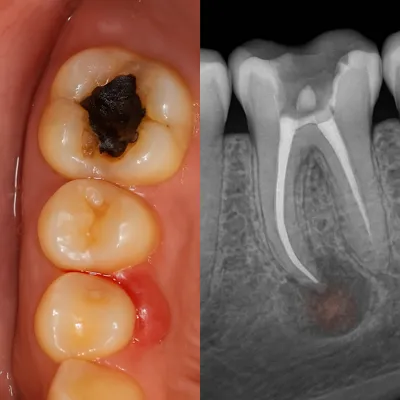

دندان عقل در انتهای دهان قرار دارد و بهخوبی تمیز نمیشود؛ همین موضوع احتمال گیر غذایی، التهاب لثه و عفونتهای مکرر را بالا میبرد. عفونتهای تکرارشونده میتوانند به دردهای مداوم و حتی دردهای مزمن فک منجر شوند.

با گذشت زمان، فشار دندان عقل به دندانهای کناری میتواند باعث آسیب به دندان مجاور، پوسیدگی بیندندانی یا تحلیل استخوان موضعی شود؛ مشکلاتی که درمان آنها ساده نیست.

درد ضرباندار، بوی بد دهان، تورم لثه یا ترشح میتواند نشاندهنده التهاب یا عفونت باشد. در چنین شرایطی ممکن است ابتدا کنترل عفونت و سپس جراحی انجام شود تا هم بیحسی بهتر اثر کند و هم تجربه درمان آرامتر شود.

اغلب به دلیل محل نادرست تزریق یا عفونت شدید بافت بوده است؛ در بافت عفونی ابتدا باید عفونت کنترل شود تا بیحسی مؤثر عمل کند.